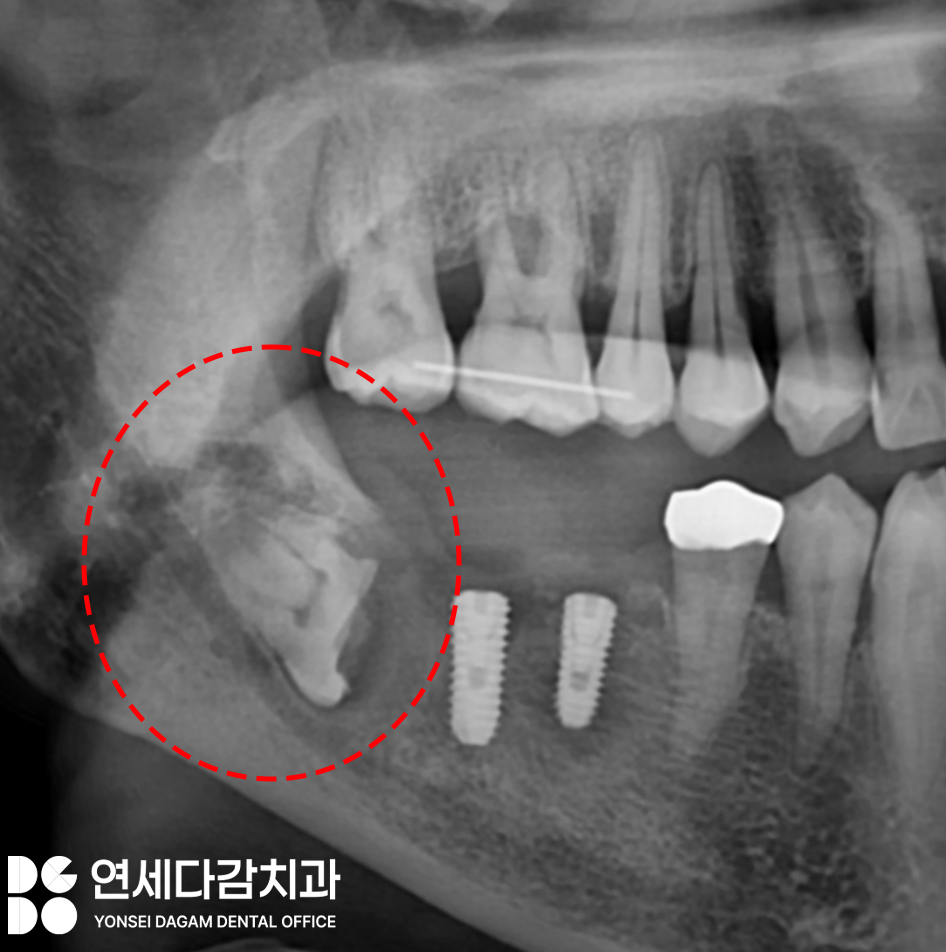

오금역 치과 에서

치관절제술을 시행하면

어떤 형태가 되는지 보여드리겠습니다.

이렇게 염증을 유발하는

치관을 절제하여

치근만 남은 상태로 잇몸을 봉합합니다.

이런 과정을 통해 신경이 손상될

걱정이 없을뿐더러 음식물이 끼는 문제를

해결했기 때문에

불쾌한 냄새와 염증 또한

사라질 수 있습니다.

이렇게 다른 부위에 임플란트로

치료가 완료될 때까지도

올바르게 절제된 사랑니는

치조골 내에 남아있어도

문제를 일으키지 않는 것을 확인할 수 있습니다.